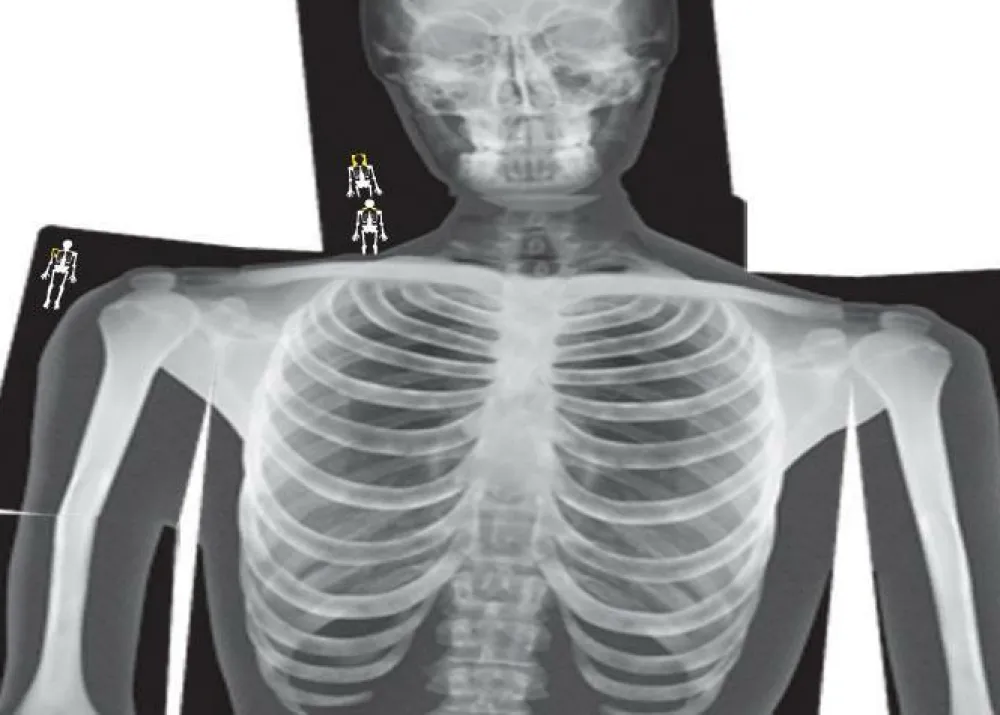

Hvordan ser menneskeskelettet ud? Og hvordan sidder knoglerne sammen? Det kan dit barn blive klogere på med disse flotte røntgenbilleder, som viser hele kroppen på en ny og sjov måde.

- Ægte røntgenbilleder

- 18 forskellige røntgenbilleder af dele af kroppen

- Kan bruges med lysboks/lysbord, overhead eller blot holdes op mod vinduet